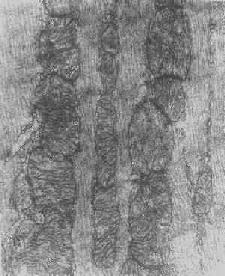

图1-8 心肌细胞线粒体

线粒体为线状、长杆状、卵圆形或圆形小体,外被双层界膜。外界膜平滑,内界膜则折成长短不等的嵴并附有基粒。内外界膜之间为线粒体的外室,与嵴内隙相连,内界膜内侧为内室(基质室)(图1-8)。在合成甾类激素的内分泌细胞(如肾上腺皮质细胞、卵甾滤泡细胞、睾丸的Leydig细胞等),线粒体嵴呈小管状。内外界膜的通透性不同,外界膜的通透性高,可容许多种物质通过,而内界膜则构成明显的通透屏障,使一些物质如蔗糖和NADH全然不能通过,而其他物质如Na+ 和Ca 2+等也只有借助于主动运输才能通过。线粒体的基质含有电子致密的无结构颗粒(基质颗粒),与二价阳离子如Ca2+及Mg2+具有高度亲和力。基质中进行着β氧化、氧化脱羧、枸橼酸循环以及尿素循环等过程。在线粒体的外界膜内含有单胺氧化酶以及糖和脂质代谢的各种转移酶;在内界膜上则为呼吸链和氧化磷酸化的酶类。